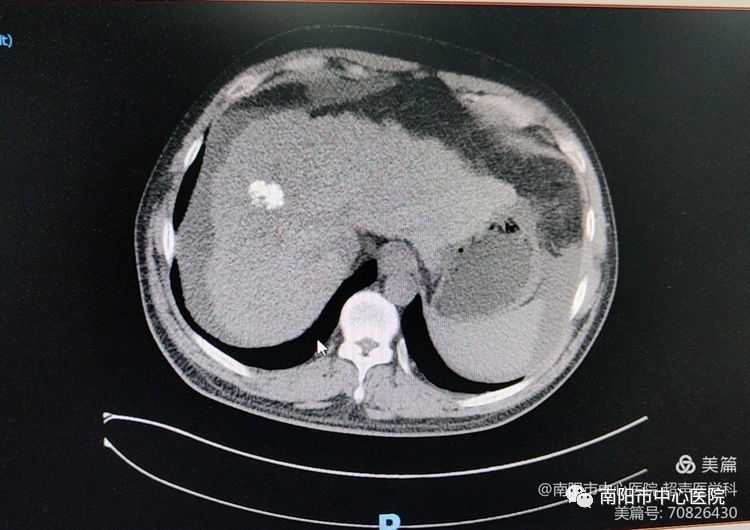

術(shù)前常規(guī)超聲探查,腫瘤位于肝S8,大小約31*20*18mm,周邊可見肝中靜脈、門脈右前支包繞。

術(shù)前行超聲造影,可見腫瘤動脈期呈高增強,形態(tài)欠規(guī)則。